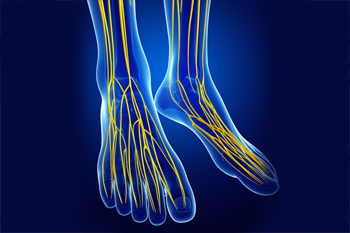

Charcot-Marie-Tooth disease is a rare inherited disorder that affects the peripheral nerves, which are responsible for controlling muscles and relaying sensory information. This condition gradually damages the nerves, often leading to muscle weakness and decreased sensation in the feet and lower legs. People with Charcot-Marie-Tooth may develop high arches, curled toes, and an abnormal gait due to the weakening of foot and leg muscles. Over time, the condition can result in balance issues, foot deformities, and difficulty walking. Symptoms often begin in childhood or early adulthood and typically progress slowly. While there is no cure, treatment options like custom orthotics and supportive footwear can help manage discomfort and improve mobility for those living with this lifelong condition. If you have this condition, it is suggested that you are under the care of a podiatrist who can help you to manage Charcot-Marie-Tooth disease.